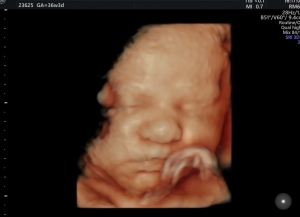

Sie können sich rund um die Uhr selbst den gewünschten Termin buchen. Besuchen Sie ggf. vorab den „Schwangerschaftskalender“ und dann die unsere Terminvergabe auf